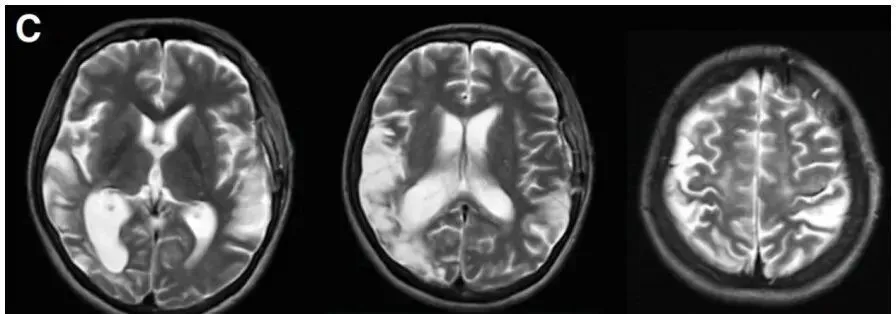

术后23天MRI复查未发现新发缺血性或出血性病变,恢复状况良好。

术后复查显示患者脑部供血明显改善,肢体麻木、视物模糊等症状逐渐消失。出院后坚持规范服用抗甲状腺药物,定期复查,目前已恢复正常工作生活。